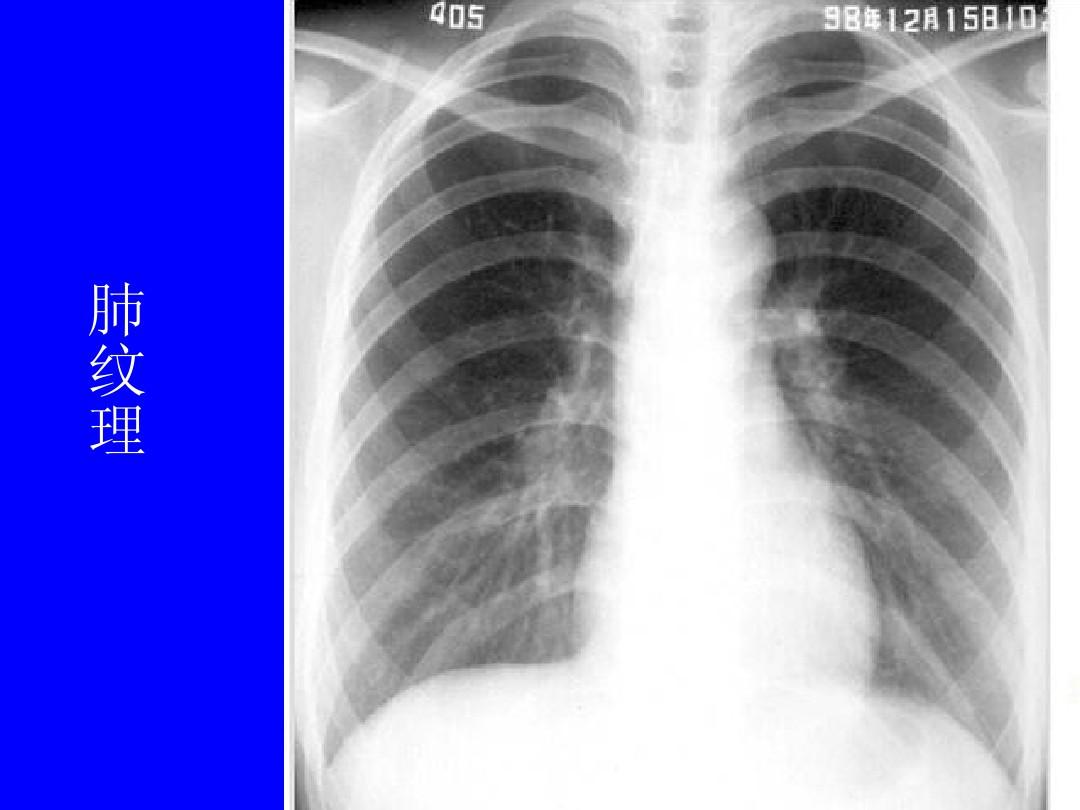

正常肺纹理(图片)

正常人的胸部

求助正常肺部x光片图片供教学用